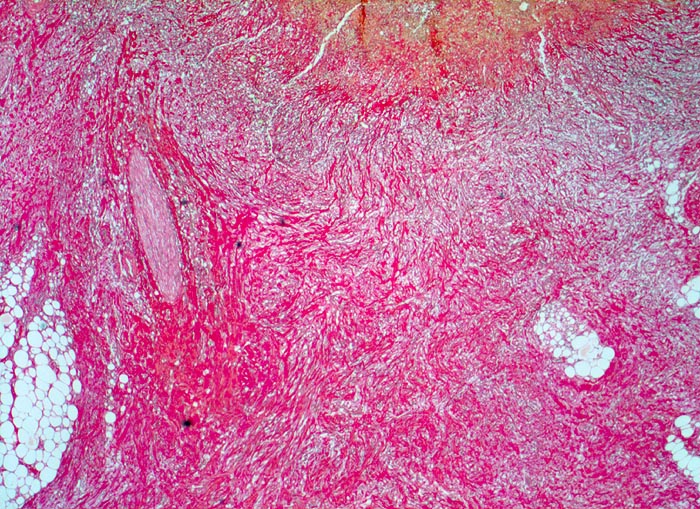

Das akute Ulkus ist rund, oval oder seltener polyzyklisch begrenzt und liegt meist im Schleimhautniveau. Das chronische Ulkus ist häufig kreisrund und im Längsschnitt trichter- oder treppenförmig. Die Schleimhautränder können lippenförmig über den Ulkusgrund hinausragen. Palpatorisch ist das chronische Ulkus aufgrund der narbigen Fibrose induriert. Die Schleimhautfalten laufen sternförmig auf das Ulkuszentrum zu. Das chronische Ulkus tritt zu 10%, das akute zu 25% multipel auf. Mikroskopisch zeigt das chronische Ulkus eine typische Schichtung (s. Bilder). Die Gefässe im Ulkusgrund zeigen eine starke Intimaproliferation mit teilweiser oder vollständiger Obliteration der Gefässlichtung. Morphologische Veränderungen in der übrigen Magenschleimhaut geben einen Hinweis auf die Ätiologie des Ulkus (Typ B oder C Gastritis).

• Schichtung: Detritus, oranges Quellungsfibrinoid, Granulationsgewebe, Narbe.

• Im Ulkusgrund arrodierte Arterie mit Intimafibrose und Abscheidungsthrombus.